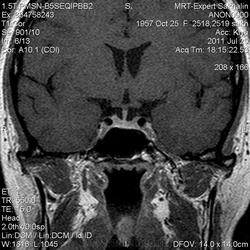

Женщина.6 лет назад выявлено образование левой доли нейрогипофиза.Пришла на контроль.

Постконтраст

Мне самой показался случай не совсем ясным, но динамик четко показывает участок с отставанием в контрастировании, воронка смещена вправо-о чем  думать бедному начинающему специалисту?